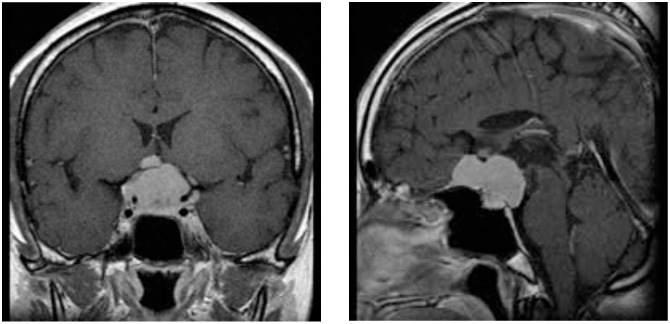

症例2は巨大斜台髄膜腫の症例です。歩行障害・嚥下困難などの症状をもち来院されましたが、腫瘍の大半を切除し、歩いて帰宅することが出来ました。海綿静脈洞部分の腫瘍は取ると合併症が出現するため、この部分は意図的に残しガンマナイフ治療を計画しています。

図2 頭蓋底髄膜腫 48歳女性 歩行障害、嚥下困難で来院

術後MRI:海綿静脈洞への浸潤部を除き

摘出、歩行障害改善し退院